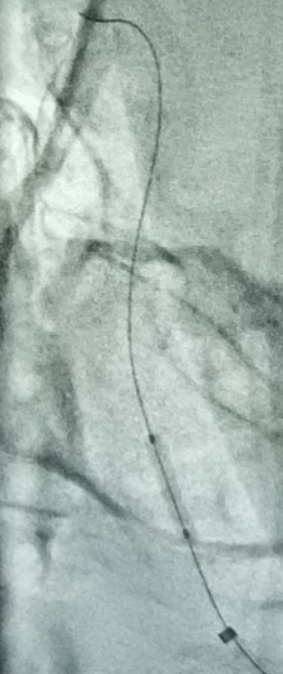

Echelon-10微导管、200cm FATHOM微导丝配合技术通过闭塞节段,微导管内路途提示进入右侧大脑后动脉。

留置300cm FATHOM微导丝,撤出微导管后造影,似乎有了一点正向血流,但压力不够,被逆向血流冲淡。